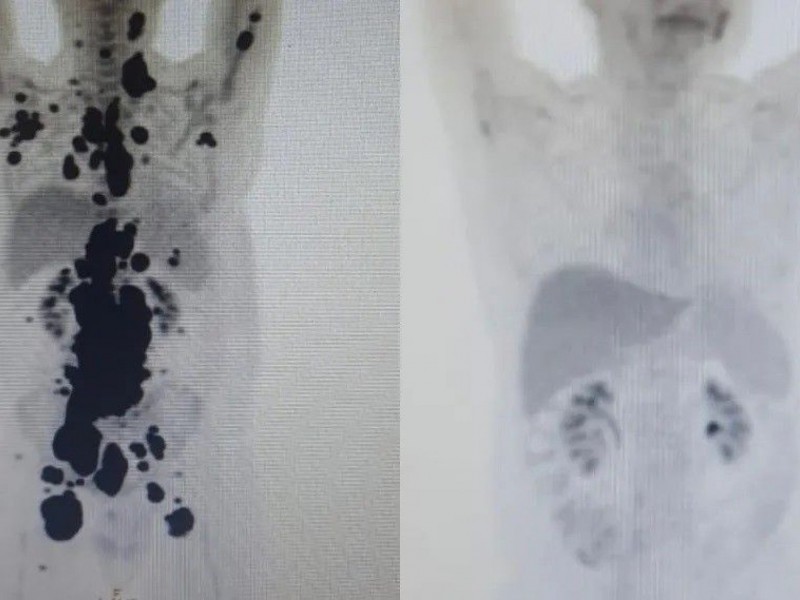

Quando Paulo já estava prestes a receber cuidados paliativos, ou seja, quando já estava em vias de ser preparado para um estágio final da vida, ele foi submetido ao tratamento de terapia celular em abril deste ano, no Sistema Único de Saúde (SUS). Em apenas um mês, teve remissão completa do câncer.

Atualmente, 14 pacientes foram tratados pela rede pública utilizando a técnica, e todos tiveram remissão de ao menos 60% dos tumores. No segundo semestre, segundo publicação feita na nesta segunda-feira pelo Hemocentro, outros 75 pacientes devem ter a chance de participar do estudo clínico.